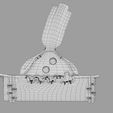

神经肌肉接头示意图